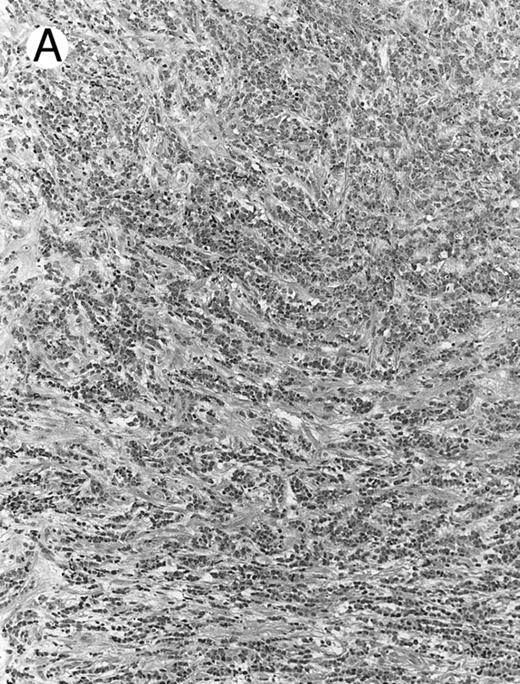

Histologically, the lymphomatous infiltrate was diffuse or patchy, with angiocentric and angiodestructive growth being observed in 30 cases (88.2%) (Figs 1 and 2). The cytologic composition was variable from case to case, including predominance of small cells, medium-sized cells, or large cells, or a mixture of these cell types (Fig 2 and 3). The tumor cell nuclei frequently showed irregular foldings and granular chromatin (Fig 2B). The larger cells possessed distinct nucleoli. The cytoplasm was moderate in amount and often pale. Karyorrhexis was usually prominent. Zonal tumor cell death, focal or confluent, was evident in 27 cases. In the 14 cases for which Giemsa-stained touch preparations were available, azurophilic granules could be identified in at least some of the neoplastic cells.

Blastoid NK cell lymphoma (case no. 40). (A) Biopsy shows a diffuse lymphomatous infiltrate with a prominent single-file pattern. (B) The neoplastic cells are medium-sized and possess fine chromatin. Mitotic figures are seen. There is remarkable resemblance to myeloid leukemic infiltration.

Blastoid NK cell lymphoma (n = 2).One patient presented with systemic disease, whereas 1 had localized disease at presentation. Histologically, the infiltrate was diffuse, with a prominent single-file pattern reminiscent of leukemia (Fig 8A). The neoplastic cells were medium-sized and had irregularly folded delicate nuclear membranes, fine chromatin, and tiny nucleoli (Fig 8B). Mitotic figures were easily identified.